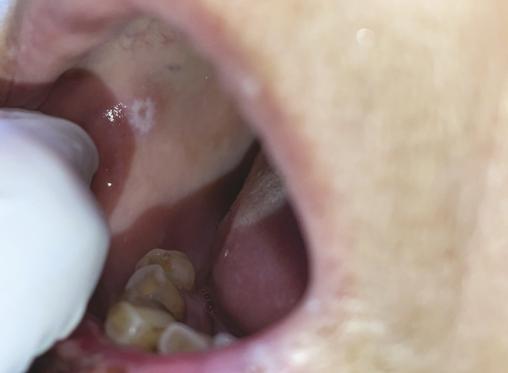

À l’examen clinique, on observe la présence de lésions érosives surmontées de croûtes sanguinolentes de la lèvre inférieure et un muguet (fig. 1 ). L’examen endobuccal retrouve une lésion recouverte d’un enduit blanchâtre (fig. 2 ). L’examen de la peau glabre met en évidence une lésion papuleuse érythémato-violacée surmontée d’un fin réseau blanchâtre au niveau de la face dorsale de la main droite (fig. 3 ) ; l’examen de la muqueuse génitale et anale est normal. Devant l’aspect érosif des lèvres, une biopsie de la muqueuse labiale et de la lésion de la main droite est réalisée : l’histologie montre un aspect compatible avec un lichen plan. La patiente est traitée par des applications quotidiennes de clobétasol en crème. Après vingt jours de traitement, les lèvres sont cicatrisées (fig. 4 ).

À l’examen clinique, on observe la présence de lésions érosives surmontées de croûtes sanguinolentes de la lèvre inférieure et un muguet (